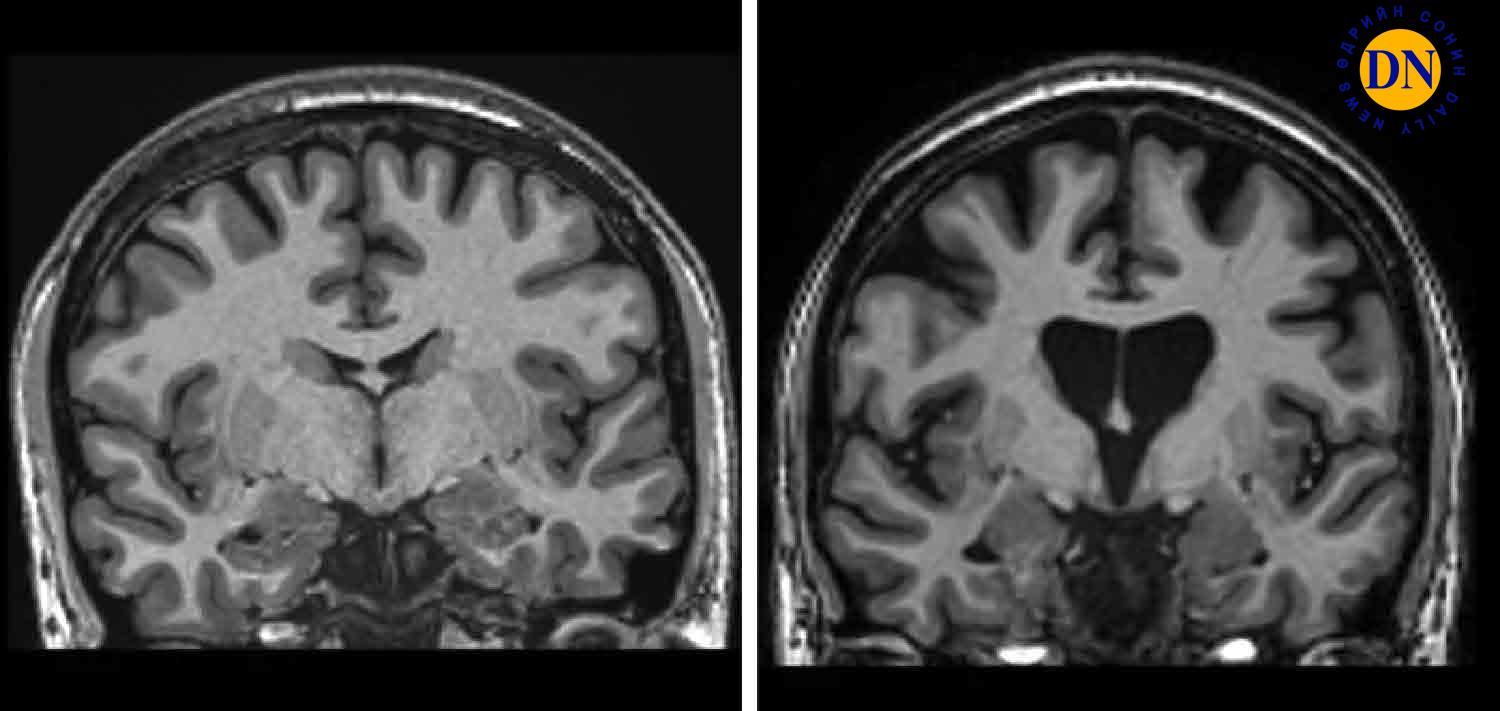

Хантингтоны өвчин бол удамшлын генийн гаралтай эмгэг бөгөөд тархины эсүүдийг устгаж, шинж тэмдгээрээ Паркинсоны өвчин, деменци, хөдөлгөөний нейроны өвчин гэгддэг саажилттай адил төстэй илэрч, хүндэрсээр үхэлд хүргэдэг өвчин юм. Хантингтоны өвчнийг тархины эсийг үхүүлдэг гентингтин гэх уургийн мутаци үүсгэдэг. Хэрэв эцэг эхийн аль нэг нь ийм мутаци бүхий гентэй байсны улмаас Хантингтоны өвчнөөр өвчилсөн бол хүүхэд нь 50 хувийн магадлалаар уг өвчин тусах аюултай аж. Тэгвэл “uniQure” компанийн эмч нар хамгийн орчин үеийн генийн анагаахын аргыг ашиглан нэг удаагийн хүнд мэс заслаар хүний биеийн гентингтиний хэмжээг бууруулах аргыг боловсруулж чаджээ. Эхлээд эмч нар хор хөнөөлгүй вирусийг генийн хувьд өөрчилж, тодорхой ДНХ-ийн дараалал агуулдаг болгодог байна. Дараа нь уг вирусыг 18 цаг үргэлжилдэг мэс заслаар микрокатетер, MRI ашиглан тархины тодорхой хэсэгт суулгана. Тэнд энэ жижиг вирус шуудангийн ажилтан шиг ажиллаж, тусгайлан бүтээсэн ДНХ-г тархины эсүүд болох нейронуудад дамжуулдаг бөгөөд улмаар тэдгээр эсүүд өөрсдөө мутацид орсон гентингтинийг бууруулдаг эсрэг төрөгчийг бий болгодог байна. Бүтэн өөрчлөгдсөн вирус суулгуулсан 29 өвчтөний нэрийг нууцалж байгаа ч энэ туршилтын эмчилгээнд оролцогчид хэлэхдээ, тэдний нэг нь эмнэлгээс гарч ажилдаа орсон, бусад нь тэргэнцэр ашиглахын оронд өөрсдөө алхаж байгаа гэжээ. Өмнө нь Хантингтоны өвчтэй хүмүүст анагаах ухаан зөвхөн сүүлчийн шатанд нь паллиатив эмчилгээ л санал болгож чаддаг байв. Харин паллиатив эмчилгээ гэдэг нь өвчнийг бүрэн эмчлэх биш, харин тухайн хүнийг дэмжих зорилготой олон хүн оролцдог, цогц тусламжийн арга хэмжээ юм байна.